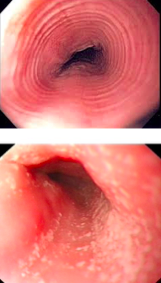

What is the difference b/t these 2 images?